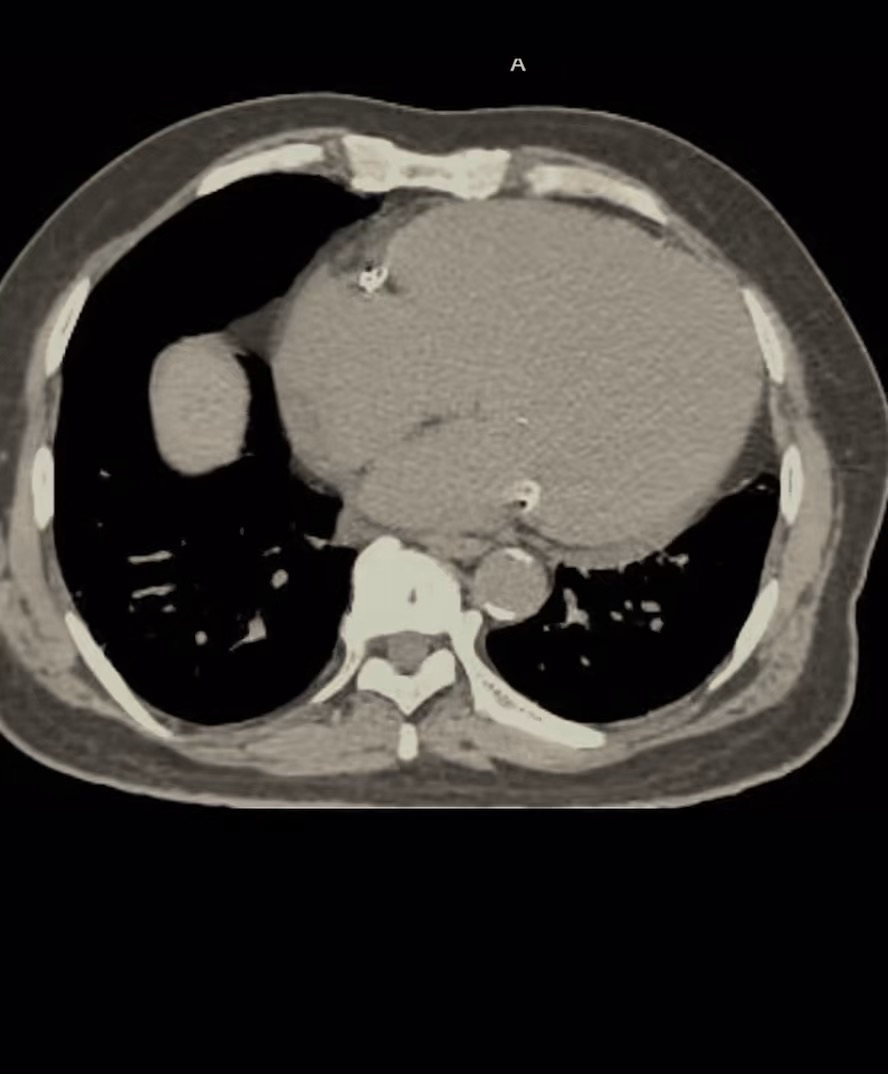

影像诊断: 广泛门脉积气并肠系膜静脉积气

正常情况下静脉是没有气体积聚的,门静脉积气是指各种原因导致的肝内门静脉主干和属支积气。“死神之征”的是肝门静脉积气(Portal Venous Gas, PVG),而非肝静脉积气。这是一种罕见但极其危险的影像学征象,通常与严重的消化道疾病相关,如肠缺血、坏死性小肠结肠炎、重症胰腺炎等肝门静脉积气是指气体在门静脉及其分支内异常积聚,CT或超声检查可见肝内门静脉,走行区域出现枯树枝状低密度影或高回声影。这种征象常伴随腹痛、腹胀、呕吐等症状,严重时可引发肠穿孔、败血症等并发症。早期文献报道其病死率超过70%,目前整体死亡率仍高达50%以上,因此被称为“死神之征”。积气若累及门静脉节段性分支,预后尤其差。